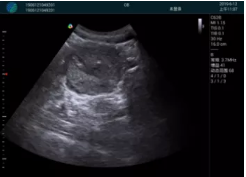

清晰顯示腺體內(nèi)低回聲快影,邊界清晰,包膜較光滑

確定進(jìn)針路徑并實(shí)時(shí)監(jiān)測抽吸針與腫塊位置關(guān)系

抽吸針進(jìn)入腫塊內(nèi)部進(jìn)行旋切

抽吸過程中可見腫塊明顯縮小,并根據(jù)腫塊位置改變針道位置

抽吸旋切后再進(jìn)行超聲復(fù)查,原腫塊區(qū)域未見殘留組織及出血